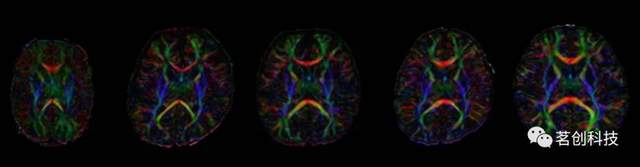

JHU-neonate-SS图谱

该图谱来自一个典型发育的足月婴儿,在出生后两天进行扫描。大小和形状与人口平均的JHU新生儿线性模板相匹配。该图谱由共同配准的T1、T2加权和DTI组成,其分割图包括130个解剖标签,包括54个皮层区域、56个白质结构、14个深部灰质结构和6个脑干结构覆盖整个大脑。手工绘制的分区图遵循成人JHU-MNI分区图,这使得成人和新生儿大脑之间的结构比较成为可能。其优点是多模态性能和当前婴儿大脑分割图中最精细的粒度。还提供了组平均T1和T2加权和DTI模板(JHU-neonate-linear和JHU-neonate-nonlinear)。

爱丁堡新生儿图谱(ENA33)

这是一组共同配准的T1和T2加权图像、DTI和33名正常发育的足月新生儿的分割图,这些新生儿在37-41周进行扫描。分割图由107个解剖区域组成,这些区域来自成人脑图谱(SRI24/TZO);